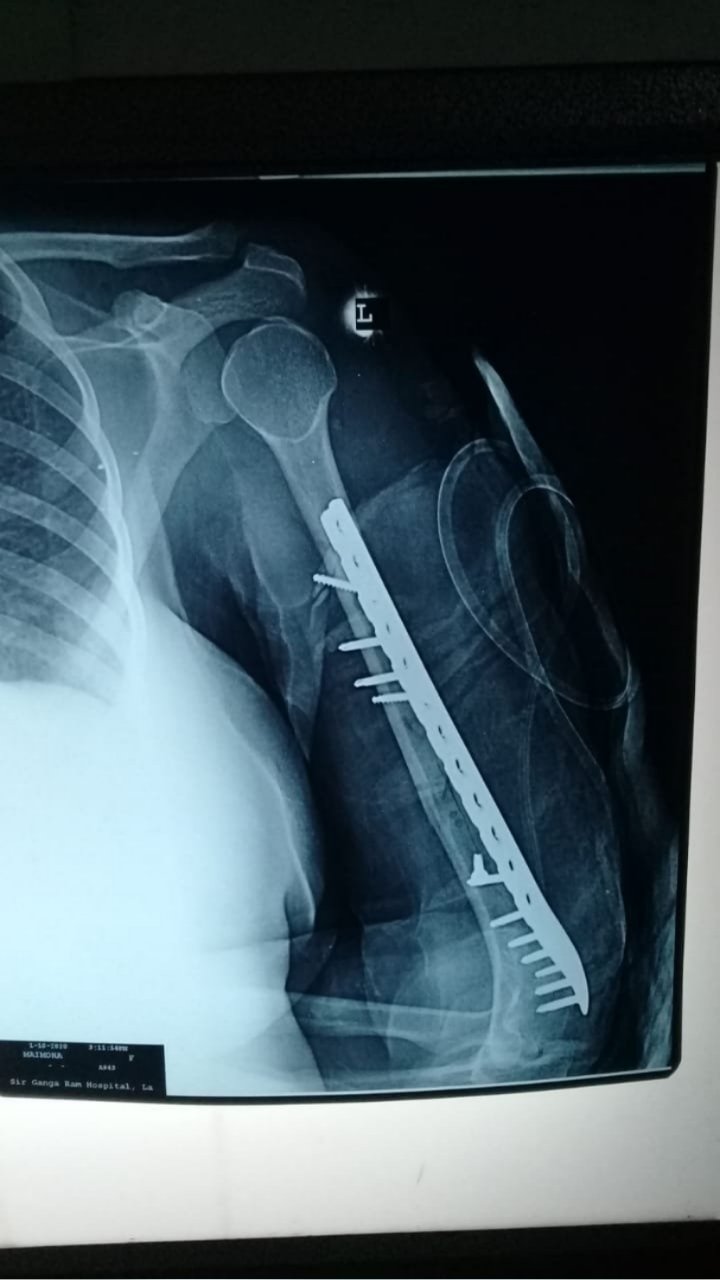

HUMERUS FRACTURE SURGERY